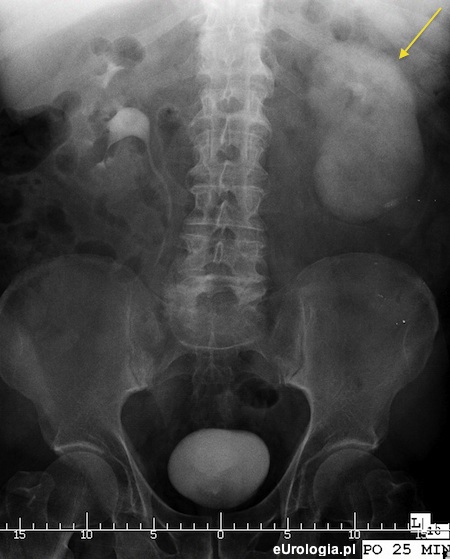

Fot. Nefrogram widoczny w urografii pacjentki z bezcieniową kamicą górnego odcinka lewego moczowodu.